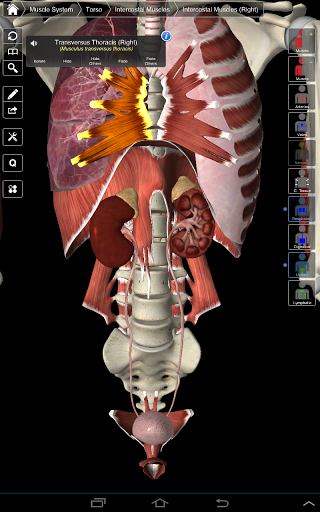

Essential Anatomy 3 représente la toute dernière technologie 3D révolutionnaire et un design innovant. Un moteur graphique 3D de pointe, construit sur mesure par 3D4Medical à partir de zéro, alimente un modèle anatomique très détaillé et fournit des graphiques de qualité exceptionnelle qu'aucun autre concurrent ne peut atteindre.

L'application représente une approche unique à l'apprentissage de l'anatomie générale. Les graphismes sont inégalés et rendent l'apprentissage, grâce à l'utilisation de contenu informatif et de fonctionnalités innovantes, une expérience riche et engageante.

La fonctionnalité intelligente trouvée dans l'application permet à l'utilisateur de dépouiller les couches de muscle via l'outil «scalpel». Cette application offre aux utilisateurs la possibilité d'activer / désactiver des systèmes sans avoir à désélectionner des structures individuelles ou à se frayer un chemin à travers une multitude d'onglets régionaux prédéfinis, comme d'autres applications.

---- Plus de 4000 structures anatomiques très détaillées

---- Mode de sélection multiple - Masquer / Fondu / Isoler des structures individuelles ou multiples